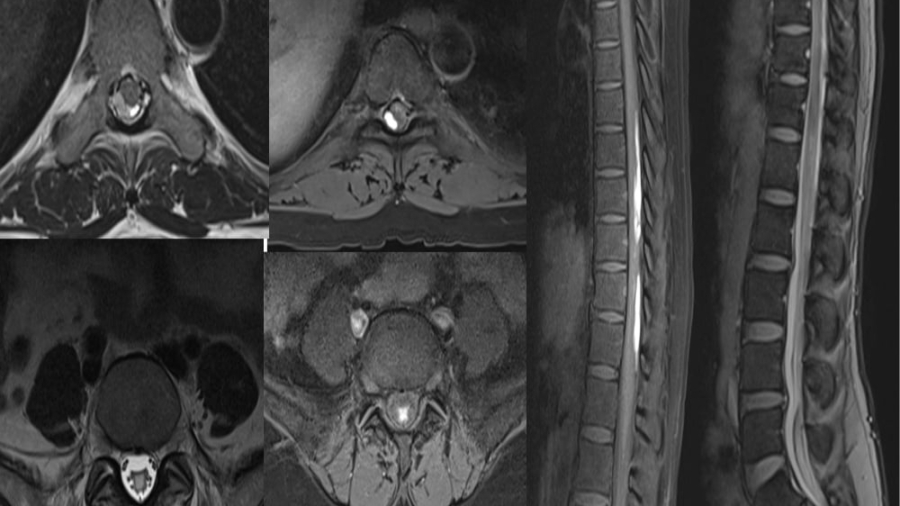

*39 year man

*K/c/o of Type 2 DM

*Newly diagnosed microcytic anemia

*Progressive weakness of left upper limb and lower limb past 6 months

*Involuntary movements of left hand